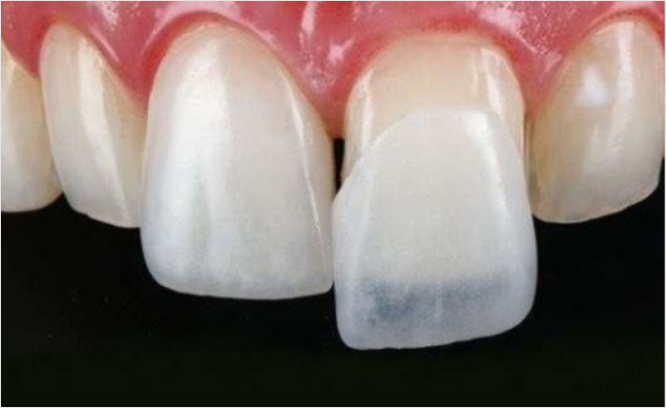

치아의 겉 표면을 최소삭제 후 얇고 자연스러운 인공치아를

치아 겉면에 덧붙여 이상적인 형태로 복원시키는 치아성형술입니다.

불만족스러운 치아의 배열, 색상, 크기 등을 수정하여

자신감있는 미소로 밝은 인상을 만듭니다.